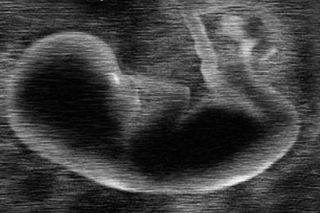

New Blood Test Can Predict Preterm Labour More Cheaply Than Sonography

A new blood test, developed by scientists and researchers at Stanford University and described in Science, detects with 75-80 percent accuracy whether a pregnancy will end in premature birth. The technique can also be used to estimate the mother’s due date as reliably as, and less expensively than, ultrasound.

Obstetricians now use ultrasound scans from the first trimester of pregnancy to estimate a woman’s due date, but ultrasound gives less reliable information as pregnancy progresses, making it less useful for women who don’t get early prenatal care. Ultrasound also requires expensive equipment and trained technicians, which are unavailable in much of the developing world. In contrast, the researchers anticipate that the new blood test will be simple and cheap enough to use in low-resource settings.